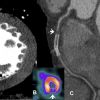

ACCF -The American College of Cardiology Foundation/American Heart Association

Multicenter Assessment of the Utilization of SPECT Myocardial Perfusion Imaging Using the ACCF Appropriateness Criteria: The ACCF and United Matters o ...